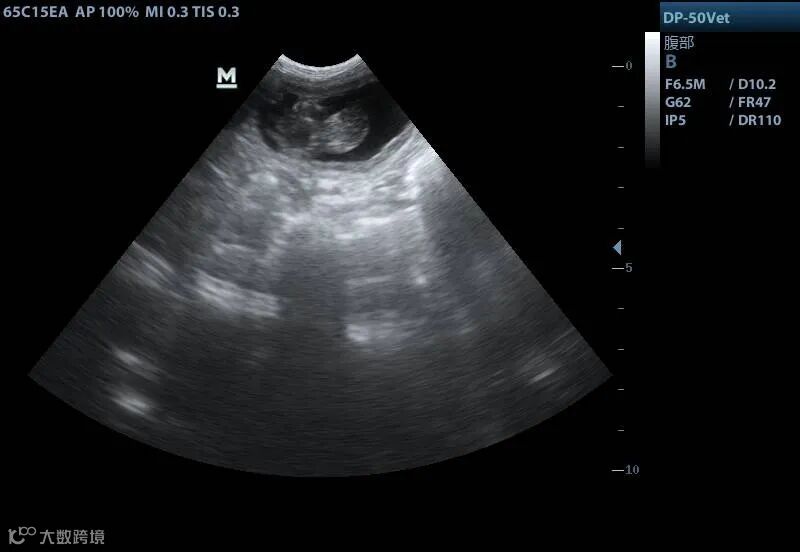

妊娠中の代理出産メス猫の超音波画像。画像提供は青島農業大学